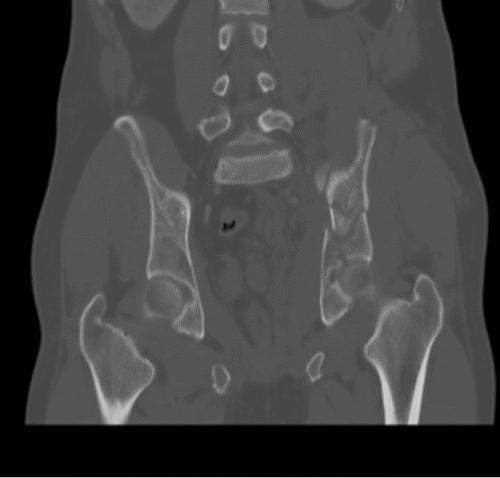

The patient's condition stabilized, and the pain was controlled with analgesia. CT showed no brain injury, but there were multiple left-sided comminuted rib fractures with displacement along the posterior and lateral aspects. In addition, it revealed the presence of hydropneumothorax; lung contusion with thoracic wall subcutaneous emphysema; right-sided mild pneumothorax; undisplaced fracture of the sternal body; herniation of the stomach into the pericardial cavity (Figure 1); no intraabdominal fluid or air and no solid organs injury; fracture of the transverse processes of the L3/L4 and L5 vertebrae; fractures of the left glenoid bone and left pelvic bone; multiple comminuted displaced fractures involving the iliac, acetabular, and pubic bones, with the displacement of the iliac bone fractures; right inferior pubic ramus nondisplaced fractures; and fracture of the left sacral alar and proximal left sacral segments (Figure 2).

Figure 2. Bone CT of Pelvic Fracture. A) Axial, B) Sagittal, and C and D) Coronal Views. Published with Permission

C) Coronal View

D) Coronal View